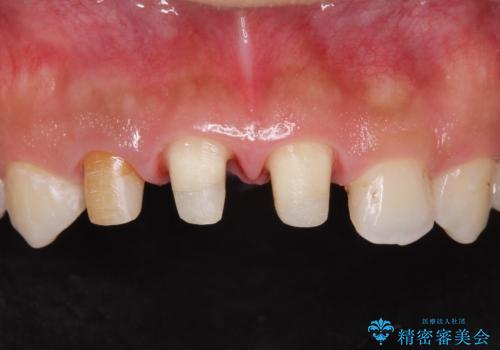

- 前歯(右上2)が黄色いとのことで来院。

レントゲンを撮ったところ前歯の被せ物が不適でした。

根管治療はご希望されなかったので(症状はなし)被せ物のやりかえ、右上2は被せ物の治療を行いました。